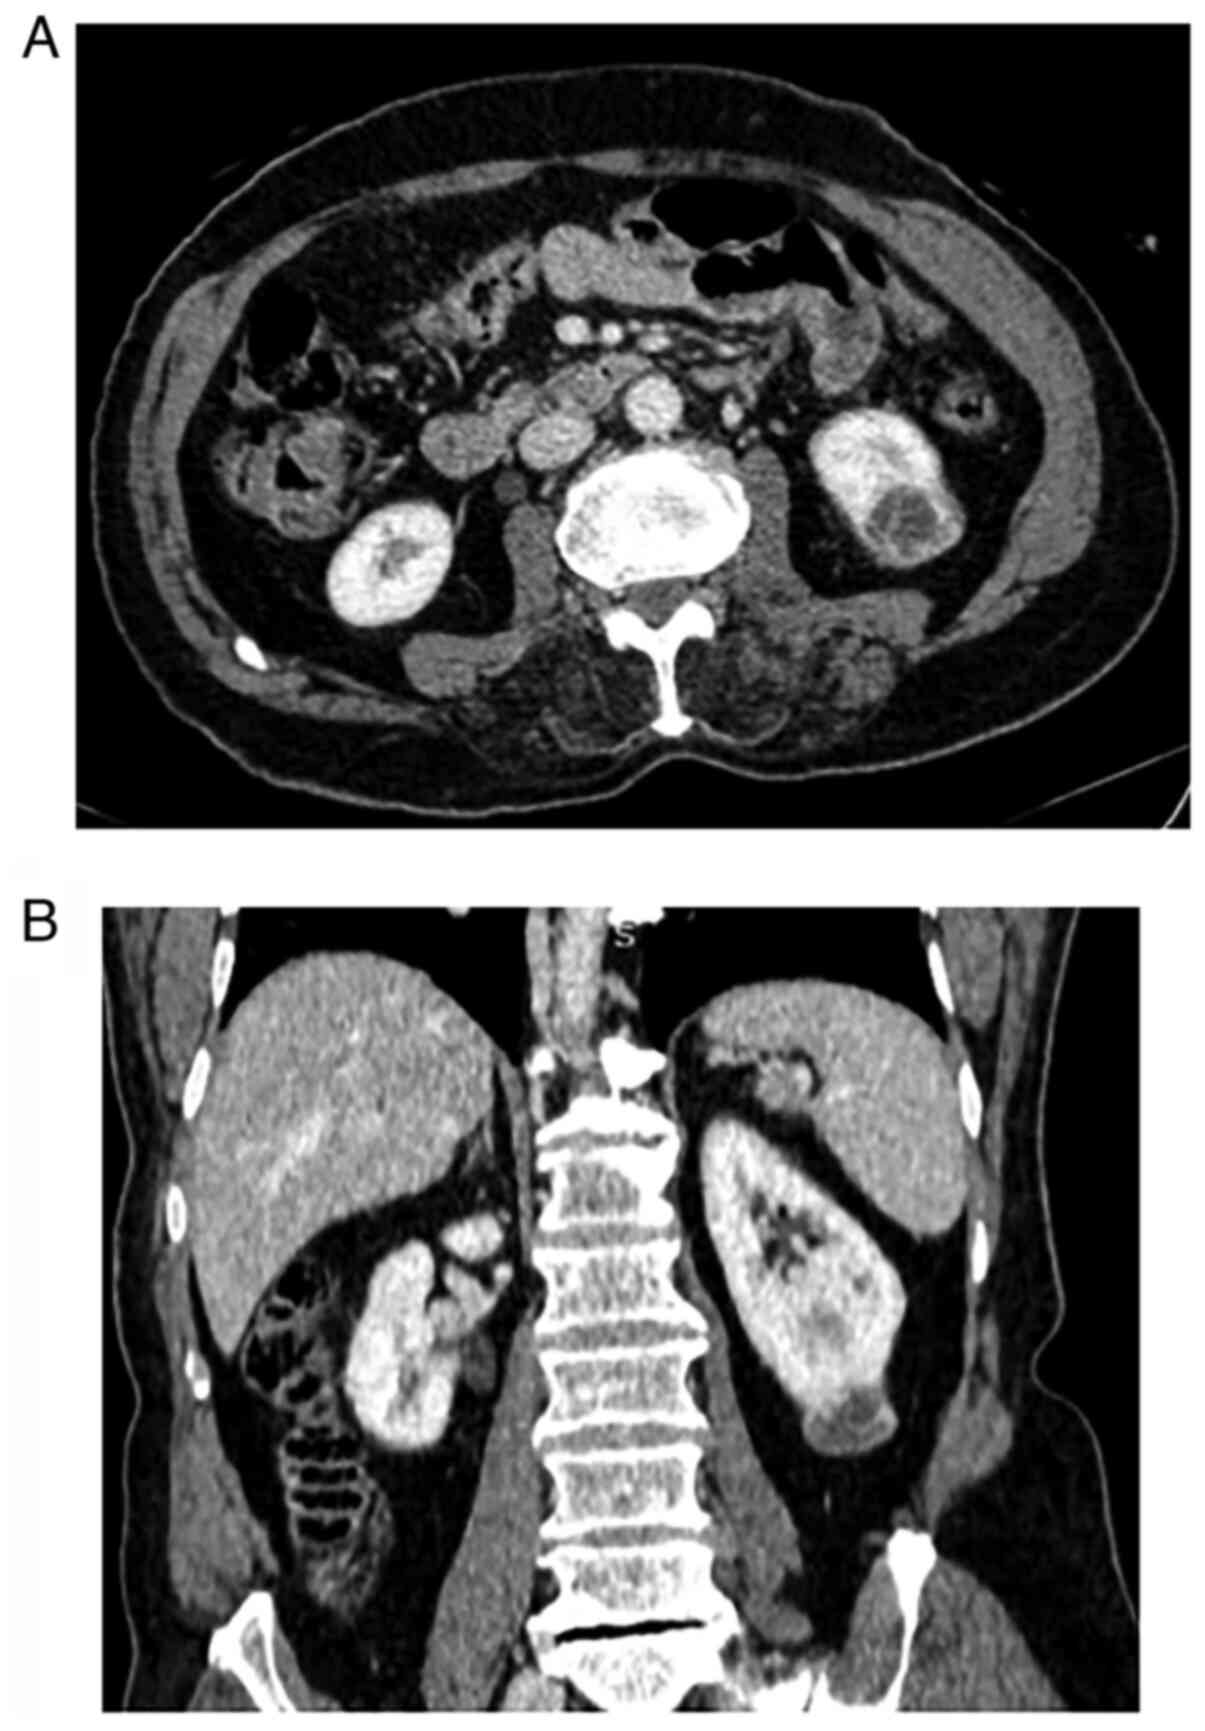

An excisional biopsy of one of the lesions revealed a nodular dermal lesion with numerous vascular channels and interlacing spindle cells. Immunohistochemical examinations (previously conducted by another center) revealed a positive reaction to CD31 (Fig. 2). He was referred to an oncology center. After a metastatic workup, a 2.5 cm enhancing mass was found in a contrast-enhanced CT of the abdomen, suggesting RCC or metastasis (Fig. 3).

Figure 3

(A) Axial and (B) coronal sections of contrast-enhanced computed tomography of the abdomen and pelvis show a left lower pole-enhancing cystic mass.